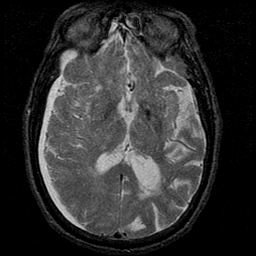

Subdural Hygroma,overlay -- Slice #25

[Home][Help][Clinical] Slice 25